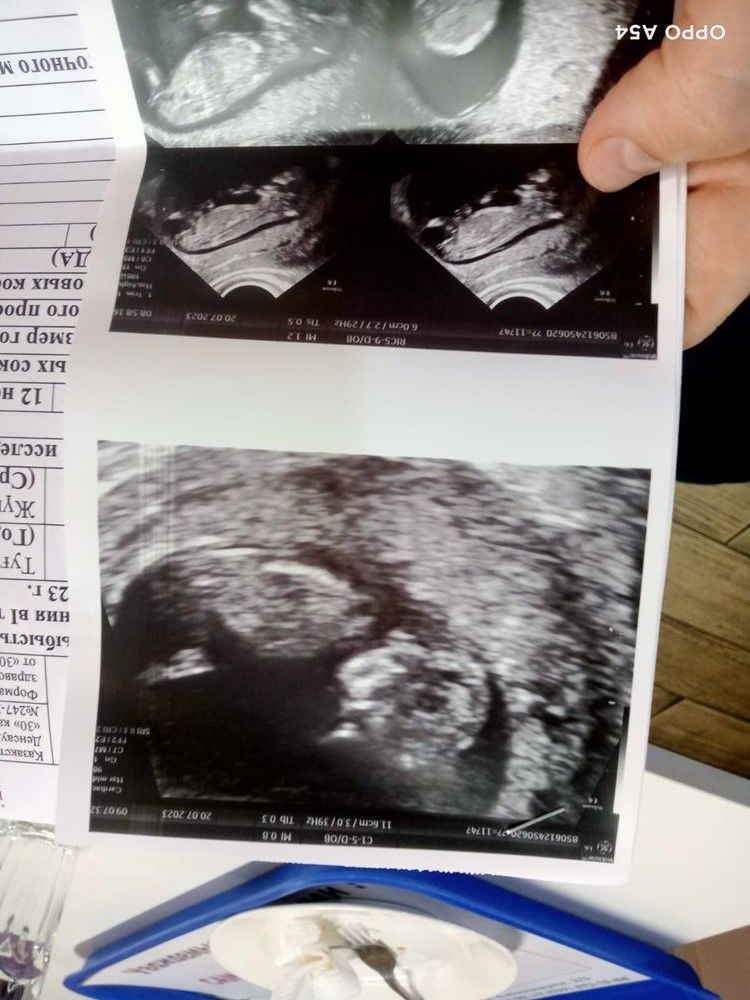

Впредверии дня Х спрошу еще раз, кого видите? (снимок с первого скрининга в 12 недель)